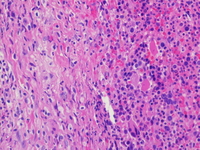

Category: Myeloid Neoplasms and acute leukemia (WHO 2016) > Mastocytosis > Systemic Mastocytosis (SM)

Moderately increased reticulin fibrosis in the area of the mast cell infiltrate (MF 2/3).